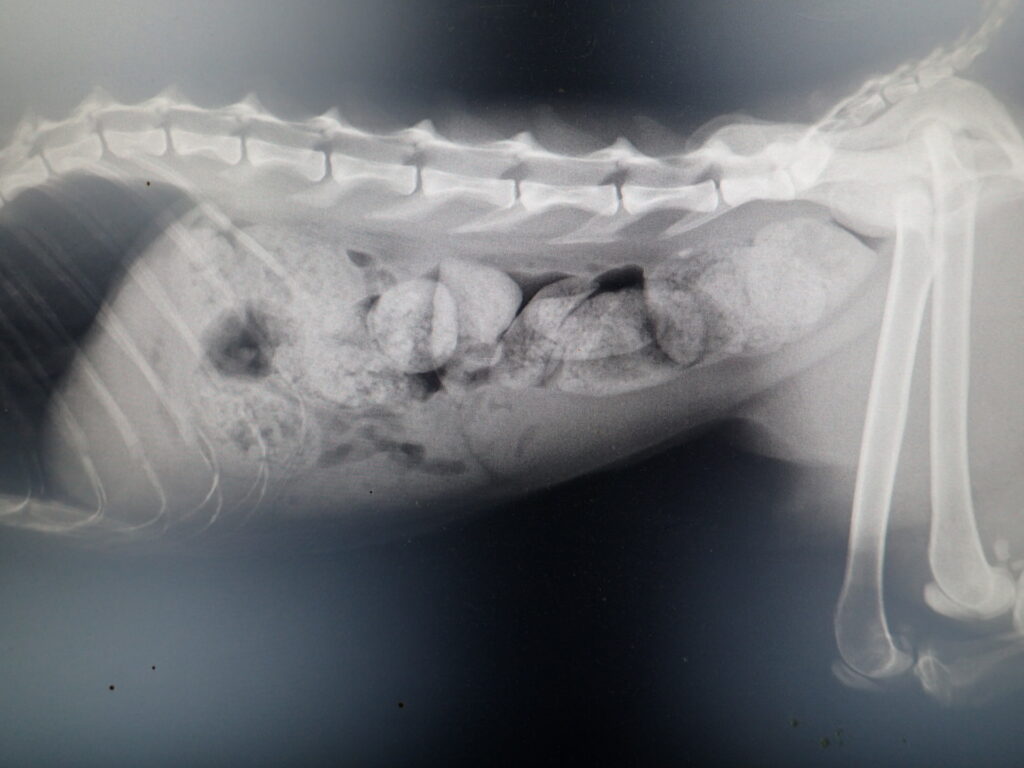

2gを7日間投与

4gを7日間投与